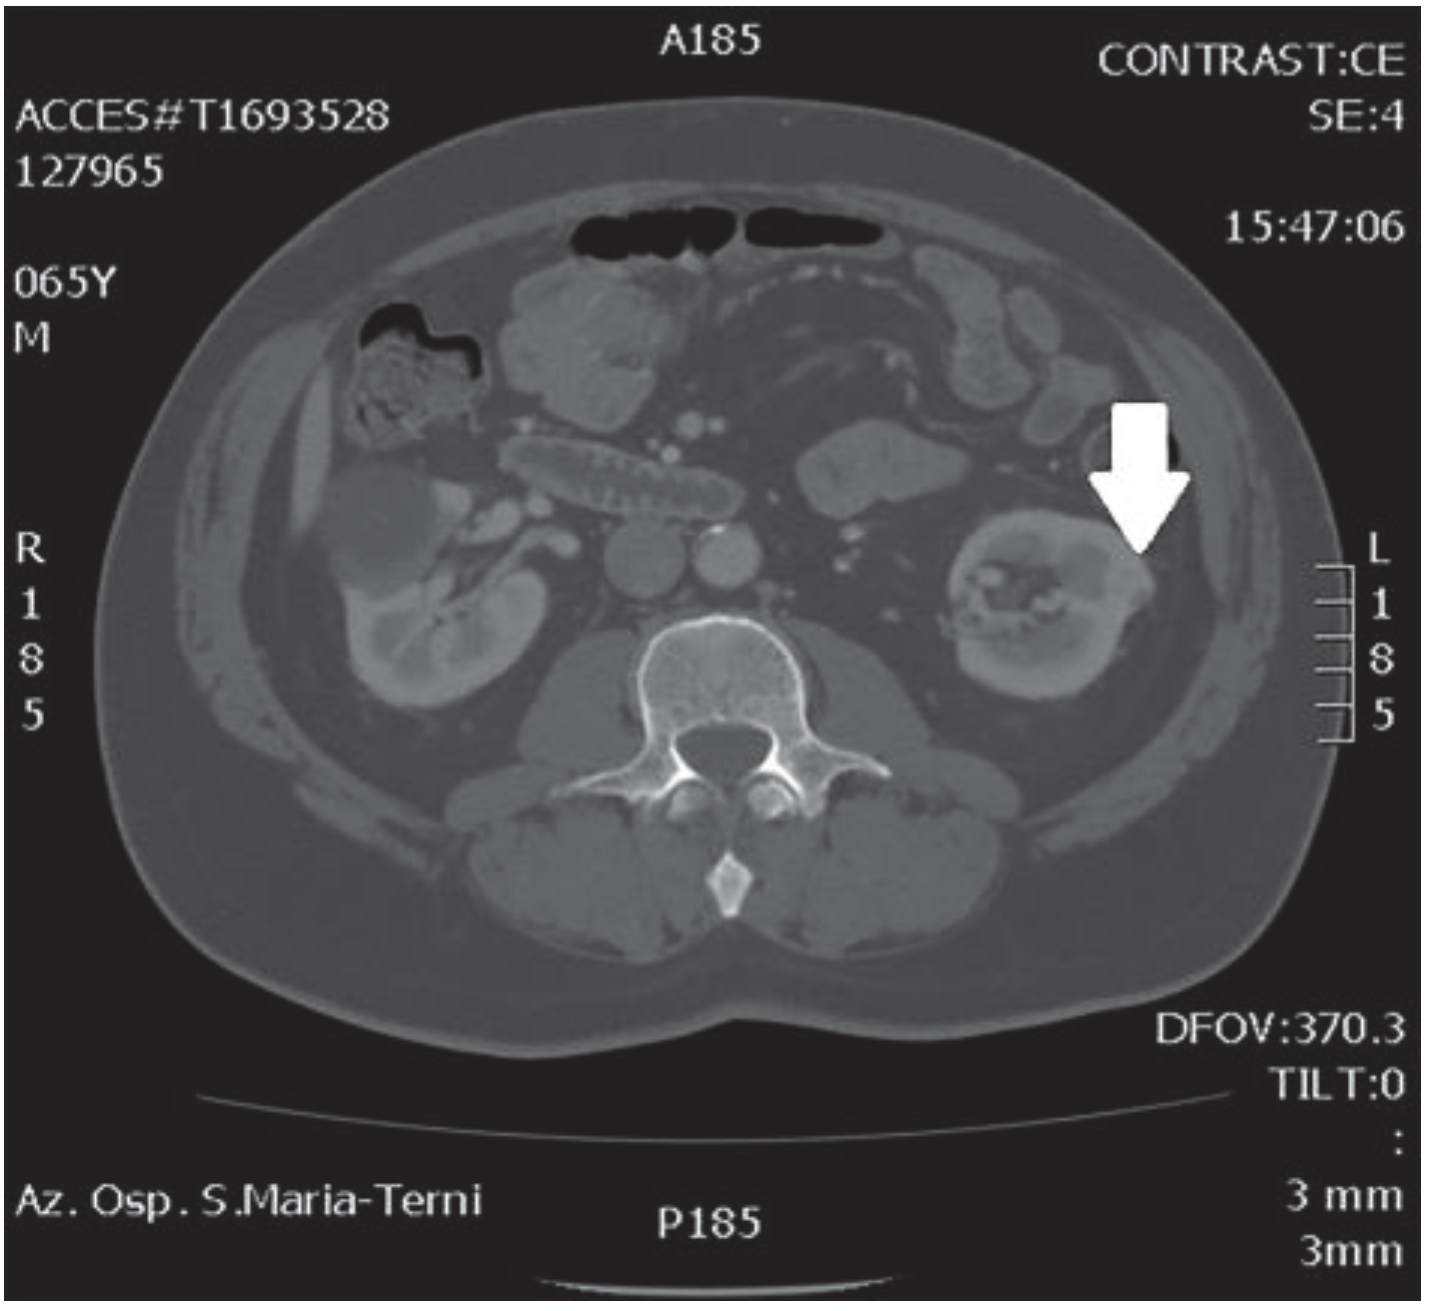

2. Case Report

| 11 | Our patient | 2018 | 66 | 25 | HTN | 2 | 4.5 | 6 (3 + 3) | T1c | 1.43 | 32 | Left |

| 10 | ||||||||||||

| 11 | Nephrectomy | 110 | 155 | 80 | 125 | Double partial | 25 | 250 (100/150) | No | - |

| 11 | 1,4 | 9 | 6 (3 + 3) | T2b | No | Oncocytoma Papillary adenoma | - | 1 | No |